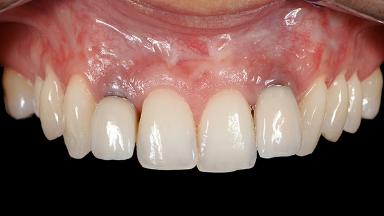

A 30-year-old woman was referred by her general dentist for evaluation of an esthetic complication related to previous implant treatment for congenitally missing maxillary lateral incisors. The patient’s chief complaint was the inadequate esthetic appearance of her smile. The case demonstrates the use of a combined approach to achieve optimal results. Two different flap designs - a tunnel technique and a coronally advanced flap - are employed based on the surgical objectives for the affected site.